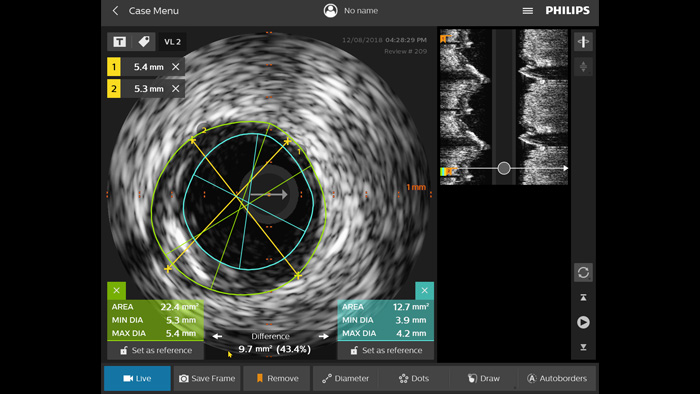

Optimice los resultados de los pacientes mediante un criterio estandarizado de IVUS. 1,2 En comparación con la PCI guiada por angiografía sola, en todos los pacientes, ULTIMATE muestra que la PCI guiada por IVUS reduce, de forma significativa, la revascularización de la lesión (TLR) impulsada clínicamente. Este beneficio se mantuvo durante tres años. Solo el 1,6 % de fallo en el vaso (TVF)* a los 12 meses y el 4,2 % de TVF a los 3 años cuando se cumplieron los criterios óptimos de la PCI guiada por IVUS.